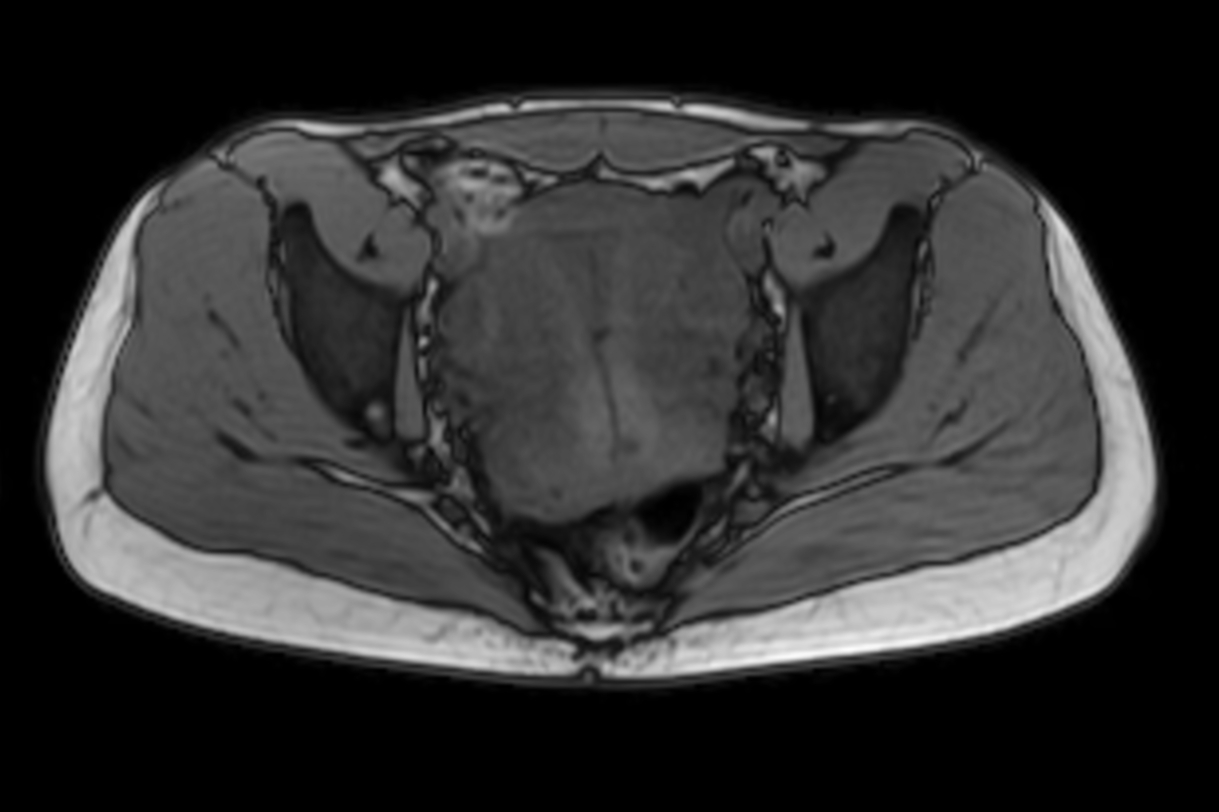

Axial MultiVane XD - T2w SPIR